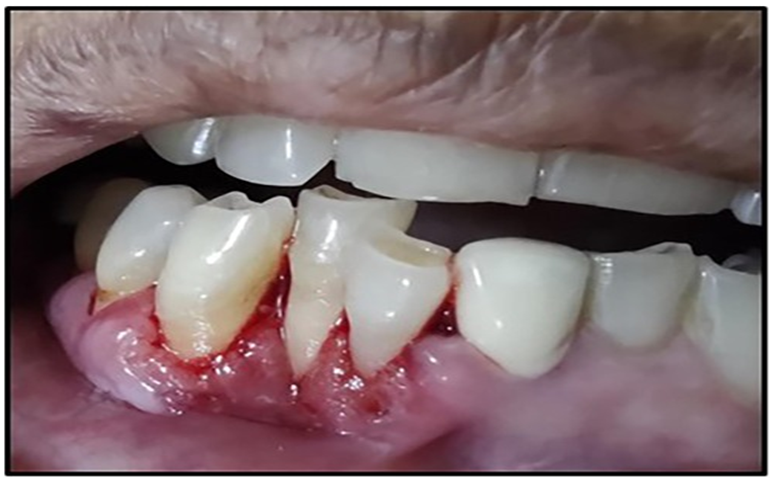

Bleeding Gums

Bleeding often happens during brushing, flossing, or sometimes even without touching the gums. This is a key sign of gum inflammation (Newman et al., 2022)

Gum Recession

As the disease gets worse, the gums pull away from the teeth, exposing the tooth roots, which can make teeth more sensitive (Lindhe et al., 2015).